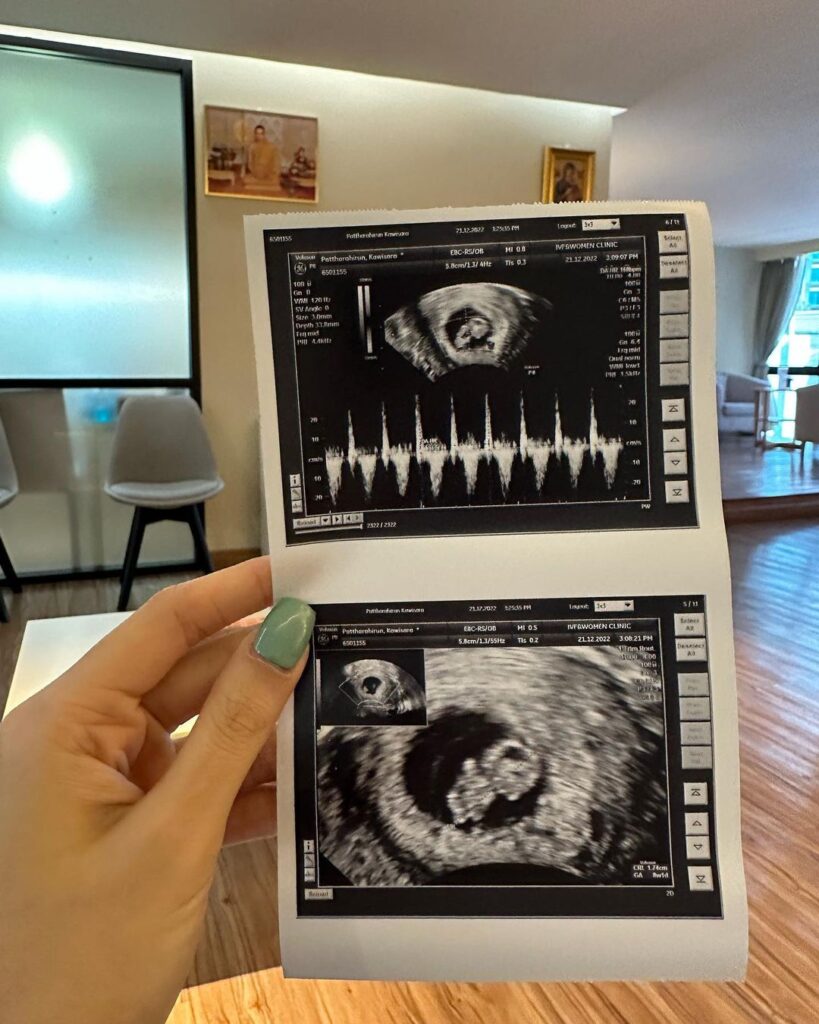

โดยเจ้าตัวได้โพสต์ภาพคู่ภรรยา อวดใบอัลตร้าซาวด์เบบี๋ในครรภ์ พร้อมกับบอกว่า “วันเด็กปีนี้ มีเด็กเป็นของตัวเองโว้ยยยยยยยยย ดีใจสุดยอด ของขวัญชิ้นใหญ่ต้อนรับปีนี้เลย !!! ขอบคุณหม่าม๊ากวาง @kwgkwg เหนื่อยอีกเจ็ดเดือนนะ เดี๋ยวเค้าดูแลเอง !!”

🤰🏻ช่วง 8w หนูสูงแค่ 1.7 cm เอง ได้ฟังเสียงหัวใจลูก คุณหมอบอกว่าหนูแข็งแรงมาก ได้ฟังเสียงหัวใจครั้งแรกรู้สึกตกใจ และดีใจจนน้ำตาไหลเลย จิ๋วแต่แจ๋ว ตัวแค่เนี๊ยะ ทำไมมีหัวใจแล้ว

🤰🏻ส่วนตอนนี้ 12w 5.5 cm แล้ว หนูโตไวมาก แขนขาเริ่มยาวขึ้น เมื่อวานดีใจที่ได้เจอกันอีกครั้ง